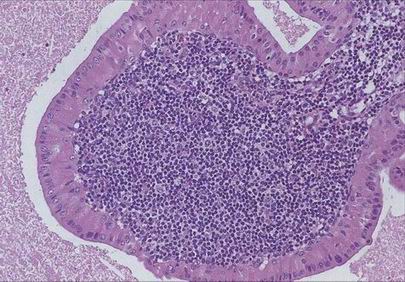

Nasopharyngeální karcinom

keratinizující

nekeratinizující (diferencovaný, nediferencovaný = lymfoepiteliom)